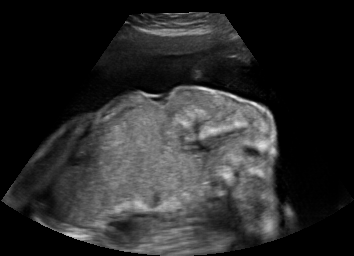

Discussion. Note that, despite both being fetal images, the simulated and the real images have substantially different anatomical contents, which makes the translation task extremely challenging. Nevertheless, our proposed framework is able to generate images with appearance strikingly close to real images, with far superior realism than its competitors. Besides sim-to-real translation, given its multi-domain conditional nature, our proposed framework without any further training can also translate images between the other domains, e.g. seg-to-real or seg-to-sim, with examples presented in Fig. 5.